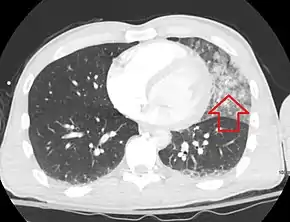

| A CT scan showing a pulmonary contusion (red arrow) accompanied by a rib fracture (blue arrow) | |

Computed tomography (CT scanning) is a more sensitive test for pulmonary contusion,[3][32] and it can identify abdominal, chest, or other injuries that accompany the contusion.[37] In one study, chest X-ray detected pulmonary contusions in 16.3% of people with serious blunt trauma, while CT detected them in 31.2% of the same people.[45] Unlike X-ray, CT scanning can detect the contusion almost immediately after the injury.[42] However, in both X-ray and CT a contusion may become more visible over the first 24–48 hours after trauma as bleeding and edema into lung tissues progress.[46] CT scanning also helps determine the size of a contusion, which is useful in determining whether a patient needs mechanical ventilation; a larger volume of contused lung on CT scan is associated with an increased likelihood that ventilation will be needed.[42] CT scans also help differentiate between contusion and pulmonary hematoma, which may be difficult to tell apart otherwise.[47] However, pulmonary contusions that are visible on CT but not chest X-ray are usually not severe enough to affect outcome or treatment.[36]